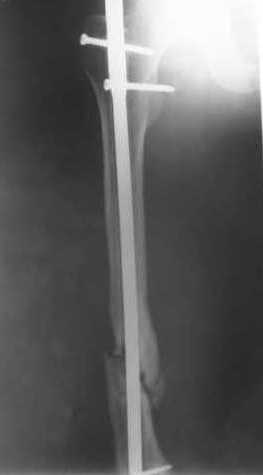

В приложении как раз видна эволюция использововшихся у нас большеберцовых гвоздей. Первый - дизайн как у UTN, второй - разнесены 45 градусные отверстия (зачем их вообще изначально так нелепо на одном уровне сделалм???), третий - убрано сиавшее лишним статическое отверстие, Herzog's bend перемещен более проксимально.